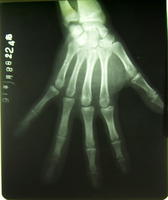

先天性並指畸形術前應拍X光片了解並指的骨骼情況,以確診軟組織並指或骨性並指。並了解指骨有無畸形,骨性並指常合併指骨發育不良,同時檢查並指間的軟組織的鬆弛程度,決定指蹼的皮瓣設計。手術時仔細檢查並指畸形中的指固有動脈發育和分布情況,分開後的兩指都應有足夠的血供,避免手指的壞死。有共用肌腱的並指,可行肌腱分離和肌腱移位術,重建手指的伸屈功能。分指時應將指神經儘可能保留於示、中、環指的橈側及小指的尺側,以便術後對指、捏物時有較好的感覺功能。